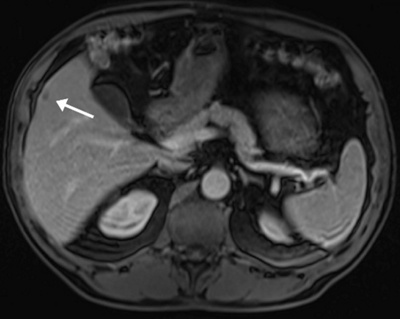

Bei Patienten mit Leberkrebs erfolgt leider oftmals die Diagnosestellung in einem Stadium, in dem eine chirurgische Entfernung des Tumors oder eine lokale Behandlung mittels Thermoablation nicht mehr möglich ist. Und auch bei Patienten mit inoperablen Lebermetastasen verlieren Chemotherapie-Regime mit zunehmender Erkrankungsdauer in der Regel ihre Wirkung. Hier kann die Behandlung der Tumorerkrankung mithilfe sogenannter lokoregionärer Verfahren sinnvoll sein. Hierbei wird in Lokalanästhesie – vergleichbar mit einer Herzkatheteruntersuchung – ein Katheter in die Leistenarterie eingeführt und unter Röntgen-Kontrolle zur Leberarterie navigiert. Dort erfolgt dann die Einbringung von Chemotherapeutika (TACE, transarterielle Chemoembolisation) oder radioaktiver Substanzen (SIRT, selektive interne Radioembolisation) in das Tumorgefässbett. Vorteile dieser Methoden ist eine vergleichsweise hohe lokale Tumorkontrollrate bei gleichzeitig guter Verträglichkeit aufgrund geringer systemischer Nebenwirkung.

body

Schematische Darstellung einer minimalinvasiven lokoregionären Behandlung bei Lebermetastasen.